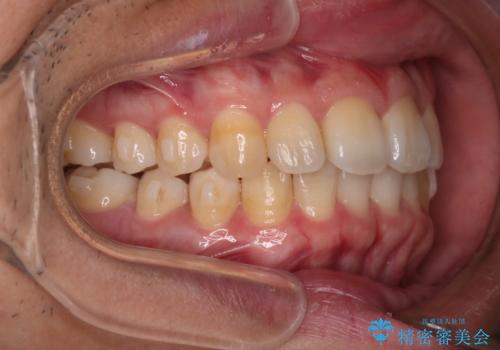

上の前歯が出ているという主訴が綺麗に改善されました。

その他の部位のがたつき、奥歯の噛み合わせも以前と比べると良くなっています。

目立たない装置で治療期間も10ヶ月と短く終了することができました。